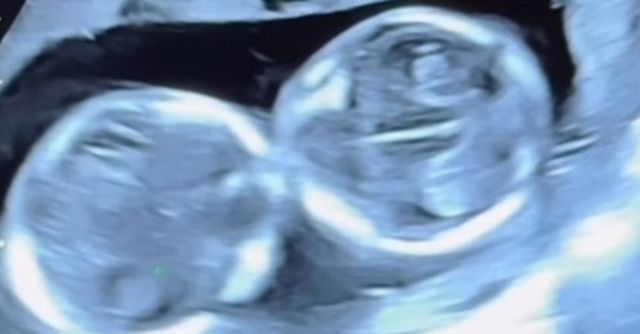

초아는 지난 27일 인스타그램 스토리를 통해 병원에서 촬영한 초음파 기록을 공개했다. 화면에는 길게 이어진 검사 사진이 보였고, 그는 1시간 넘게 정밀검사를 받은 끝에 “모두 정상”이라며 안도감을 드러냈다. 초아는 사진이 자신의 키만큼 길다며 검사에 꽤 오랜 시간이 걸렸음을 전했고, 결과를 확인한 뒤 “고마워 아가들”이라는 짧은 인사말을 남겼다.

초아 인스타그램

초아는 임신 과정을 설명하며 자신에게 자궁경부가 없어 조산 위험이 높다고 했다. 그런 이유로 배아 1개만 이식했지만, 배아가 자연 분열해 일란성쌍둥이가 되었다고 전했다. 의학적으로 약 1퍼센트 수준의 가능성이 현실이 되면서, 그는 “기적처럼 찾아온 소중한 생명”이라고 표현했다.